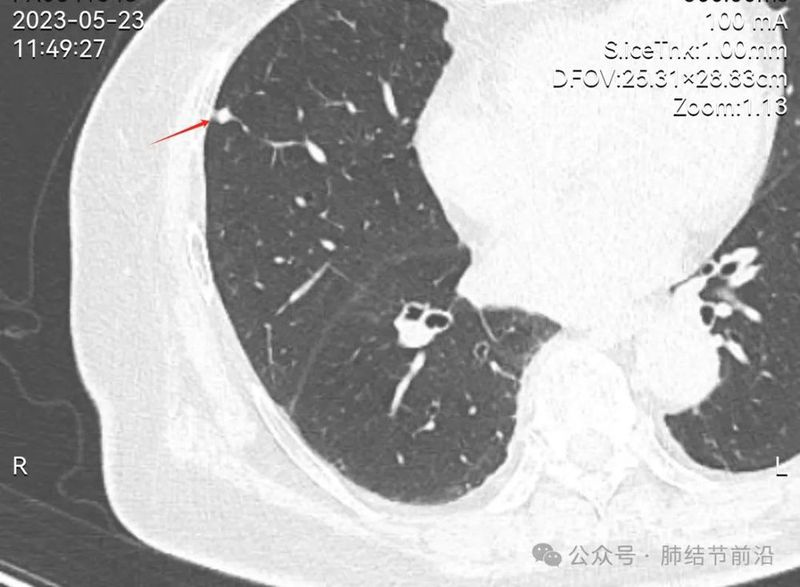

患者之后即刻前往另一家三级医院就诊,再次行薄层CT检查。这次可清晰显示为实性小结节,那么就可以排除磨玻璃结节和原位癌的诊断。考虑为陈旧性慢性炎症结节。